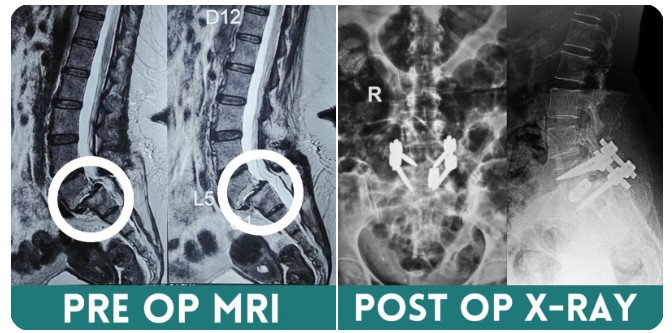

Diagnosing sciatica involves a combination of a physical examination and imaging tests. Doctors may perform tests to assess muscle strength and reflexes. Imaging tests, such as X-rays, MRI, or CT scans, can help identify the underlying cause of nerve compression, such as a herniated disc or spinal stenosis.

Diagnosing compressive myelopathy involves a combination of clinical evaluation and imaging studies. A thorough neurological examination can identify deficits and help localize the level of compression. Imaging studies, particularly magnetic resonance imaging (MRI), are crucial in visualizing the spinal cord, identifying the source of compression, and assessing its severity. Computed tomography (CT) scans and X-rays may also be used to evaluate bony structures and traumatic injuries.

The treatment of compressive myelopathy depends on the underlying cause and the severity of symptoms. In cases of acute spinal cord compression, surgical intervention is often required to relieve pressure and prevent further neurological damage. Surgical options may include decompression laminectomy, discectomy, or tumor resection.

Treatment typically begins with conservative measures such as rest, physical therapy, and pain management. If symptoms persist or worsen, surgical options like spinal fusion may be considered to stabilize the spine. Surgery is generally reserved for severe cases where conservative treatments fail to provide relief. Early diagnosis and appropriate treatment are key to managing spondylolisthesis and improving quality of life